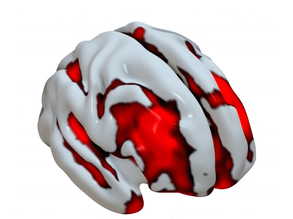

Brain Box

Rainbow Brain Rows